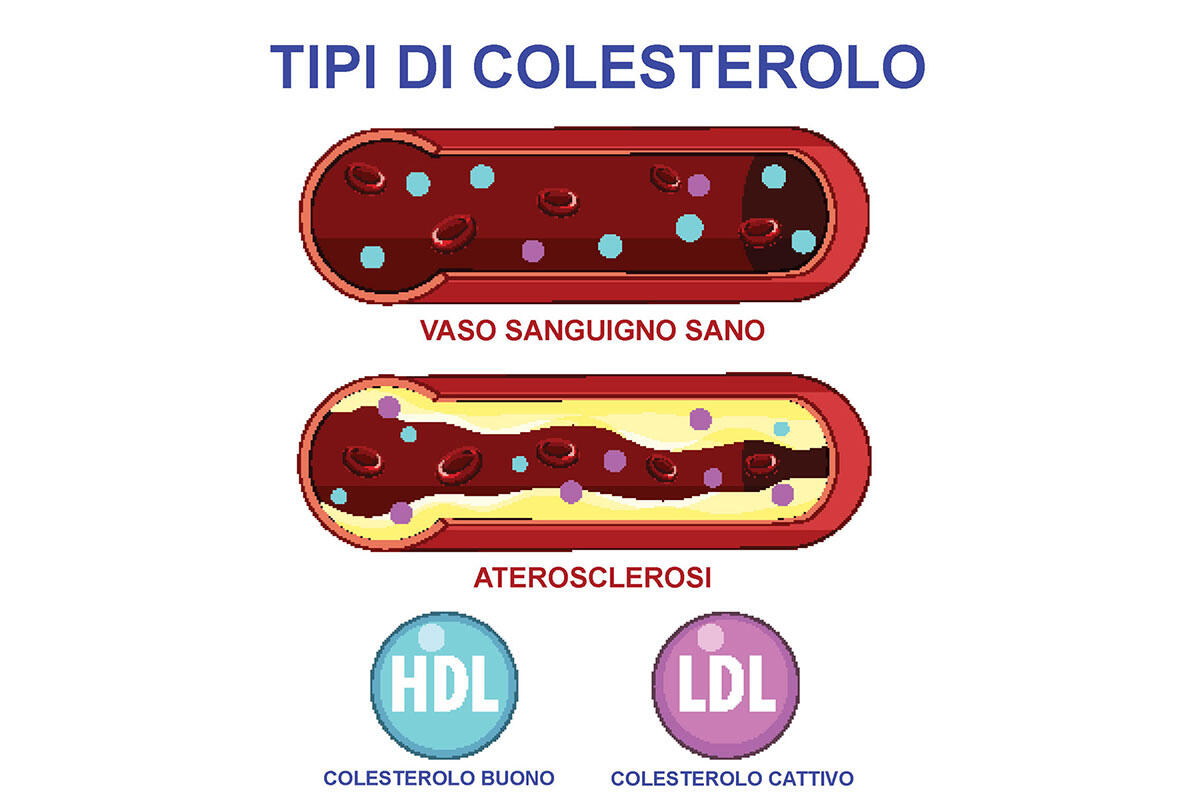

Trigliceridi e colesterolo alti vanno tenuti sempre sotto controllo: il problema non è tanto mangiare un dolcetto o il formaggio – l’alimentazione incide solo del 15% sull’ipercolesterolemia – quanto le forme legate alla familiarità. L’impegno resta comunque necessario: «Il colesterolo è di famiglia, anche papà ce l’ha alto», come ci sentiamo ripetere spesso noi medici, non è una buona scusa per non occuparsene.